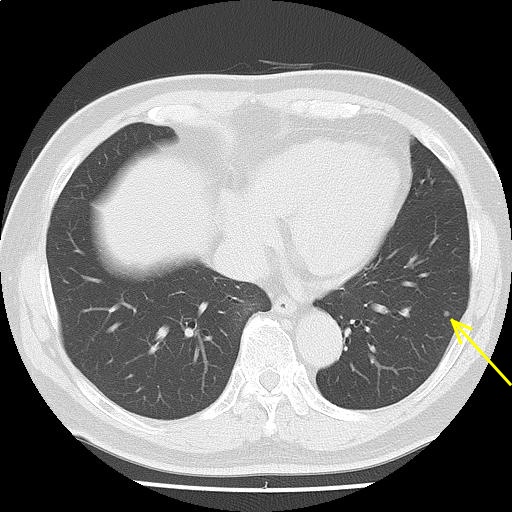

両肺下葉に小結節を認める。前回検査と比較して著変はなく、その他の肺野に明らかな異常所見を認めない。

陳旧性炎症性変化が疑われるが、経過観察を検討されたい。

縦隔リンパ節腫大を認めない。胸水を認めない。

両下葉に小結節を認める。経過観察をご検討されたい。